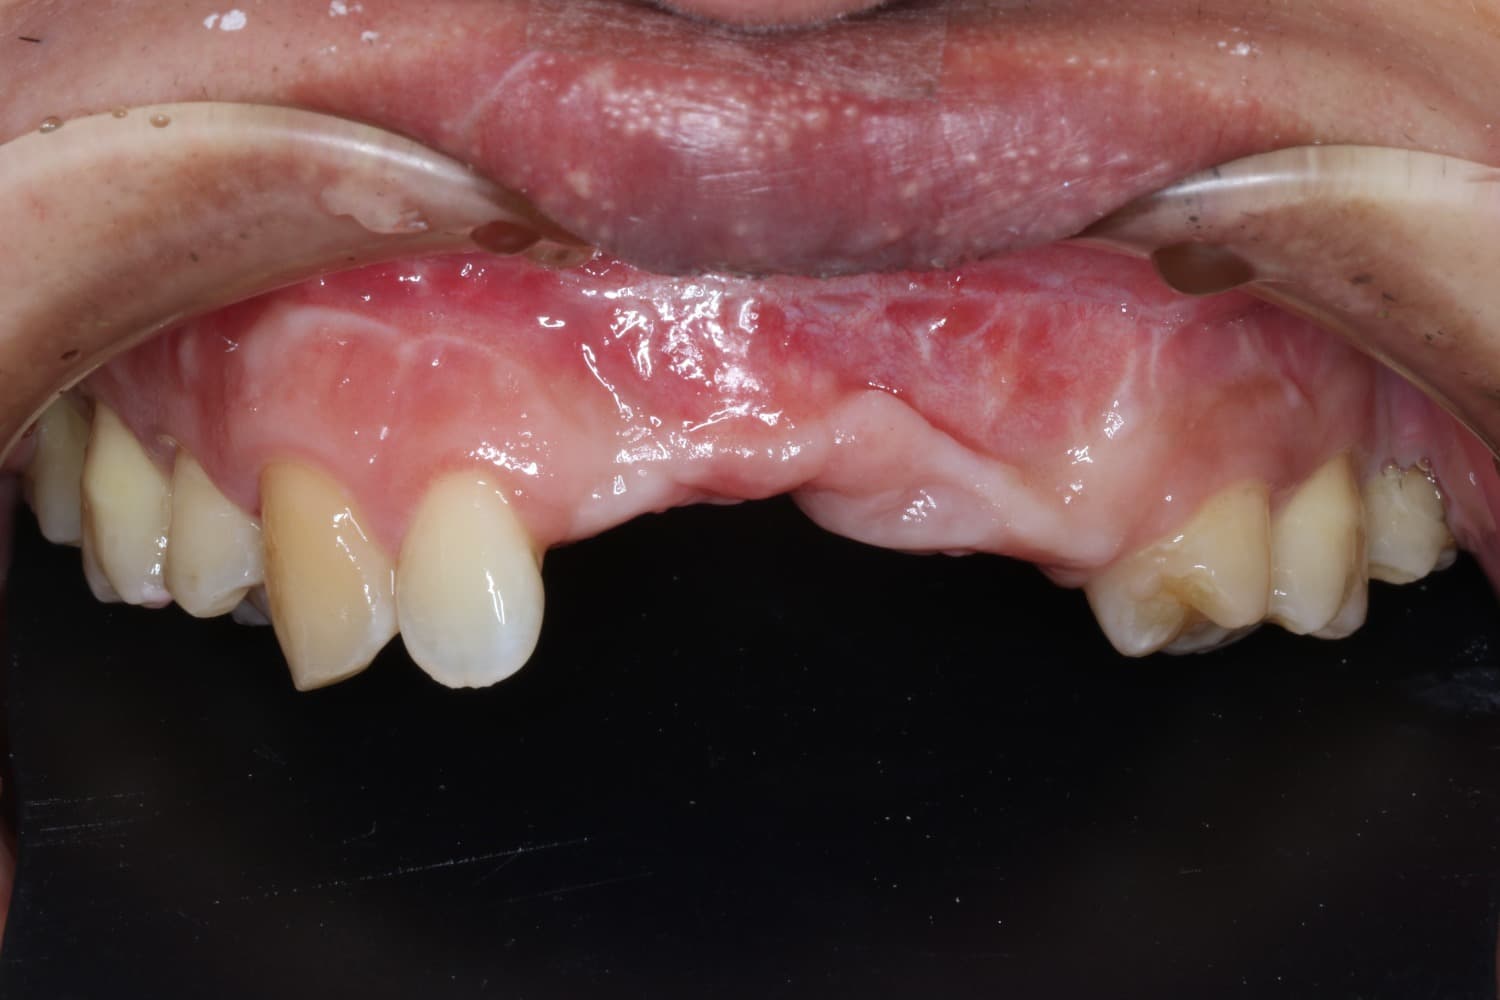

連続欠損に対するインプラント治療

Before

After

喪失した連続欠損に対してインプラントGBRCTGを行い、審美的・機能的に回復を行なった

年齢

30代

性別

男性

主訴

前歯の入れ歯を避けたいのでインプラントをしてほしい

治療期間

2年

治療回数

20回

費用

200万円

副作用・リスク

腫脹、疼痛